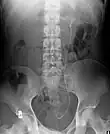

Ureteric stent

Ureteral stents are used to ensure the patency of a ureter, which may be compromised, for example, by a kidney stone. This method is sometimes used as a temporary measure to prevent damage to a kidney caused by a kidney stone until a procedure to remove the stone can be performed.

An ureteral stent it is typically inserted using a cystoscope, and one or both ends of the stent may be coiled to prevent movement. Ureteral stents are used for various purposes, such as temporary measures to prevent damage to a blocked kidney until a stone removal procedure can be performed, providing drainage for compressed ureters caused by tumors, and preventing spasms and collapse of the ureter after trauma during procedures like stone removal. The thread attached to some stents may cause irritation but allows for easy removal by pulling gently. Stents without threads require cystoscopy for removal. Recent developments have introduced magnetic retrieval systems that eliminate the need for invasive procedures like cystoscopy when removing the stent. The use of magnets enables simple extraction without anesthesia and can be done by primary care physicians or nurses rather than urologists. This method has shown high success rates across different patient groups including adults, children, and kidney transplant patients while reducing costs associated with operating room procedures.